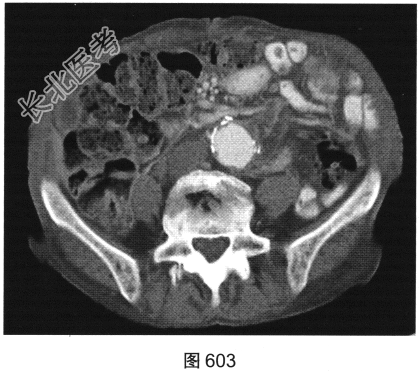

- [材料题] 患者女性,85岁,腹主动脉瘤破裂手术修复后,腹部疼痛。患者行腹部CT检查,见图603~图607。

- 多项选择题1.对该病变CT影像表现描述正确的是( )

A、腰大肌未见明确异常

B、未见主动脉再破裂征象

C、可见主动脉再破裂

D、可见腹膜后均质肿块

E、腰大肌受累

F、可见腹膜后不均质肿块